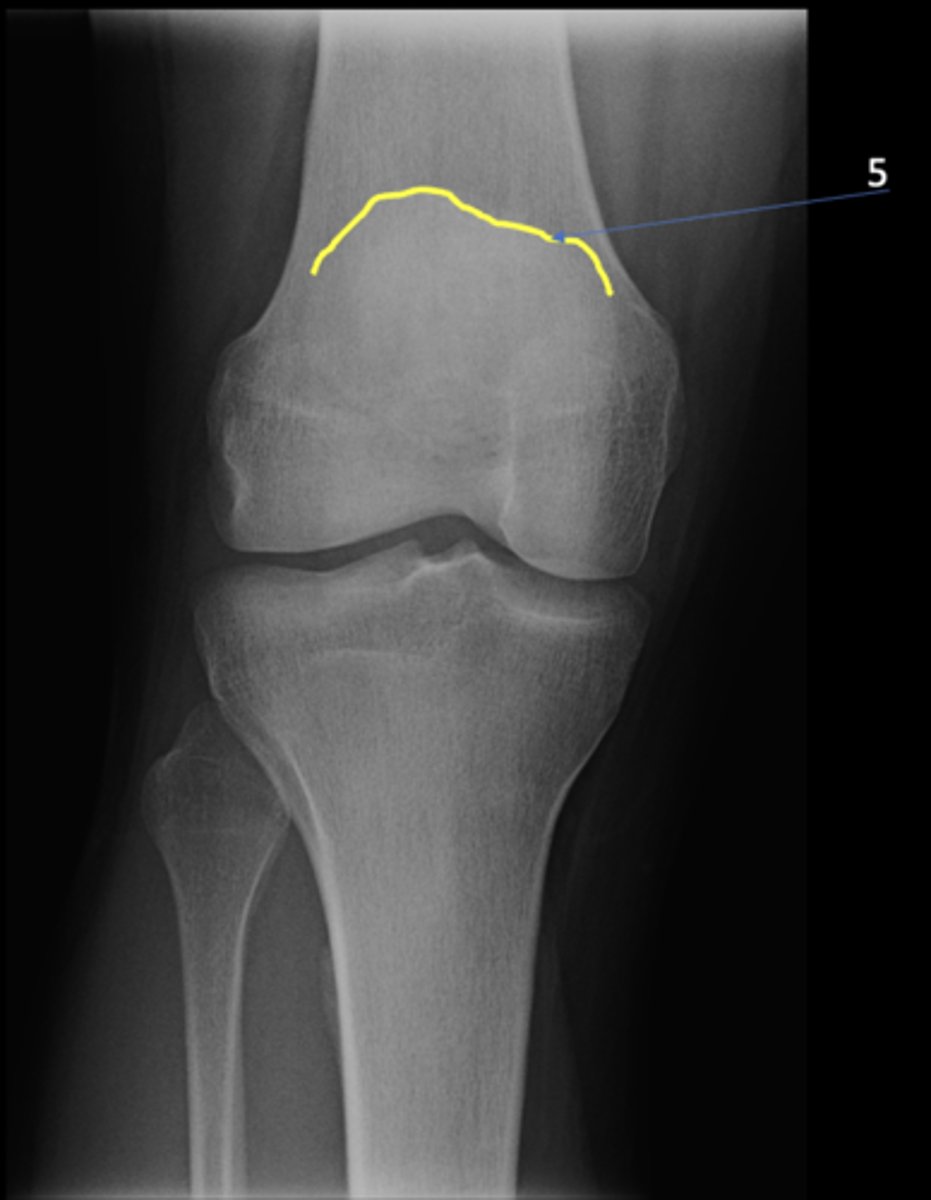

AP knee

View?

<p>View?</p>

53

New cards

Superior aspect of patella

ID 5

<p>ID 5</p>